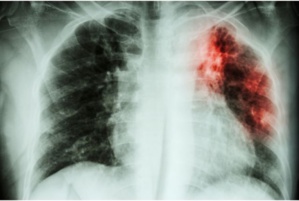

"و تتوقف الاعراض التي يصاب بها الناس على الموضع الذي يصبح فيه السل نشطا في الجسم، وعلى الرغم من أن السل يؤثر عادة على الرئتين، فهو يؤثر أيضا على الكليتين و الدماغ و العمود الفقري والجلد،

ان المغرب بالرغم من المجهودات المبذولة في مجال محاربة داء السل بحكم البرامج الوطنية والحملات التحسيسية والرفع من الميزانية المرصودة لداء السل فمازالت الارقام مقلقة حيث تم تسجيل حسب المنظمة العالمية للصحة 35000 حالة و انتكاسة جديدة مما يمثل 93 حالة لكل 100000 نسمة، يشكل منها 53 بالمئة داء السل الرئوي.